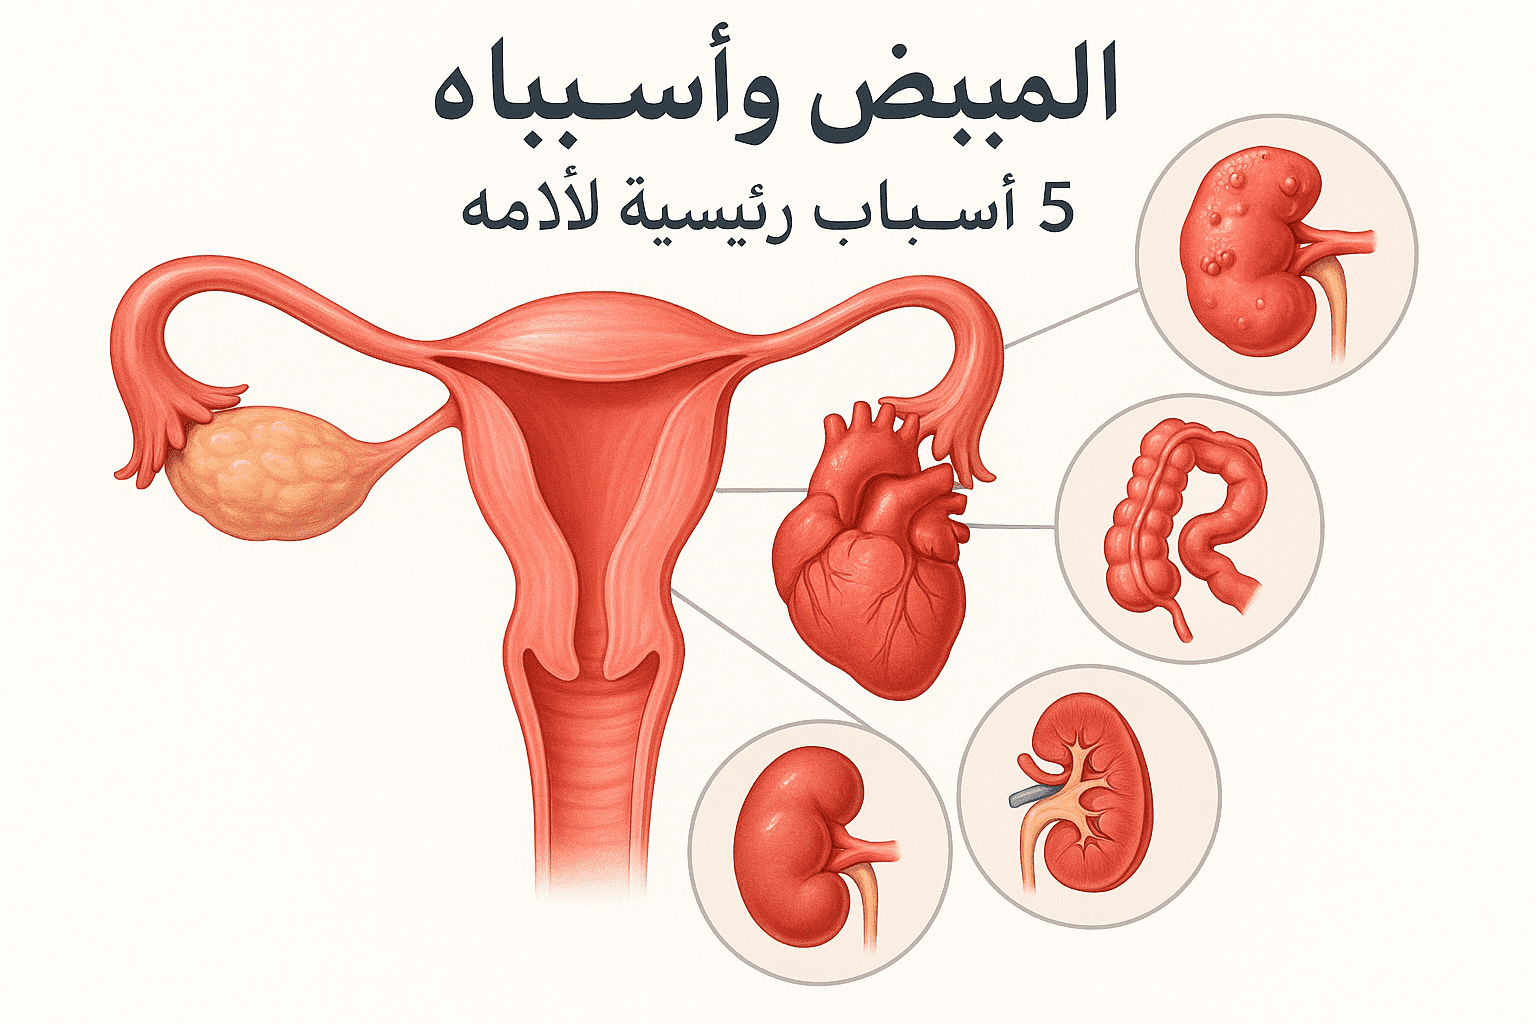

مقالات طبية من مساهمات الأطباء